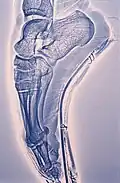

Xérographie du pied d’une danseuse dans son chausson faisant des pointes.